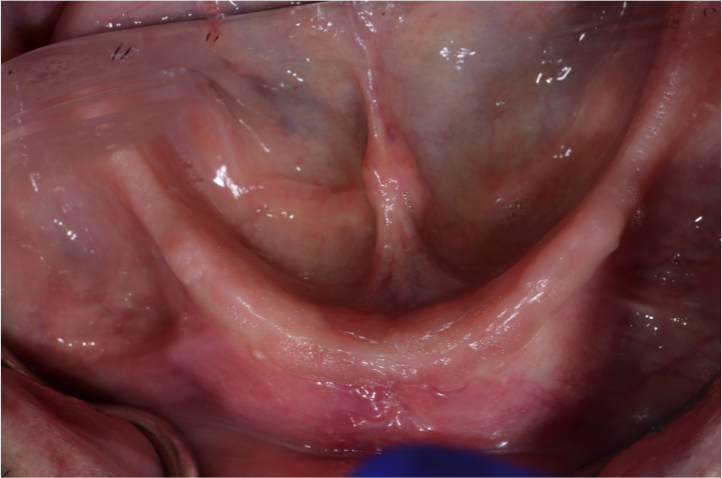

LANAP

Pinhole

LAPIP

- Laser Periodontal Therapy (LANAP)

- The Chao Pinhole® Surgical Technique